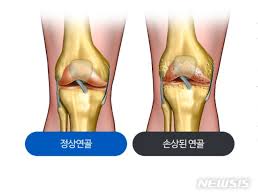

무릎 연골 손상 증상 이해하기

무릎 연골 손상 증상은 다양한 원인에 의해 발생할 수 있으며, 이는 일상생활과 운동에 큰 영향을 미칩니다. 무릎 연골 손상 증상은 주로 무릎 통증, 부종, 뻣뻣함 등으로 나타나며, 특히 무릎을 구부리거나 펼 때 '뚝' 소리가 나기도 합니다. 이러한 증상이 발생하면 즉각적인 대처가 필요합니다. 무릎 연골 손상 증상은 방치할 경우 퇴행성 관절염과 같은 이차적인 질환으로 이어질 수 있기 때문에 빠른 진단과 치료가 중요합니다.